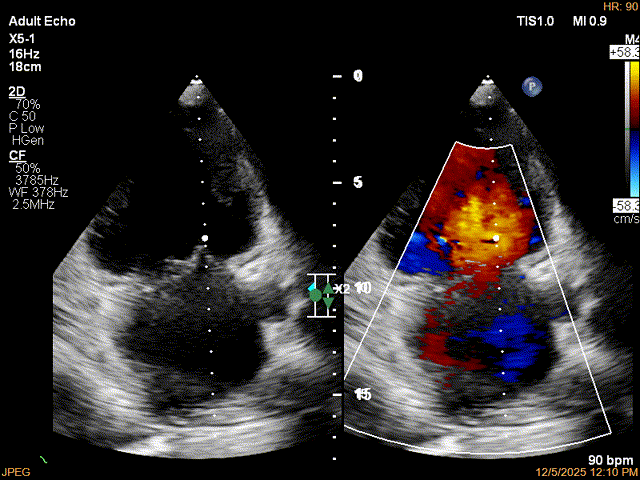

患者食道胃底静脉曲张,遂行TTE术前评估

术前TTE评估:

MR反流病因:DMR(部分腱索断裂)、Carpentier II型;

反流程度:极重度(5+),PISA法估测EROA约1.12cm²,R-VOL约98ml;

病变情况:P2-部分P3,脱垂宽度约27mm ,连枷间距11-13mm,瓣口面积7.8cm²,PML约25mm

其他:TR(重度) ,间接估测PASP约65mmHg;

预估手术难点:后叶冗长,脱垂宽度大,连枷间距大。